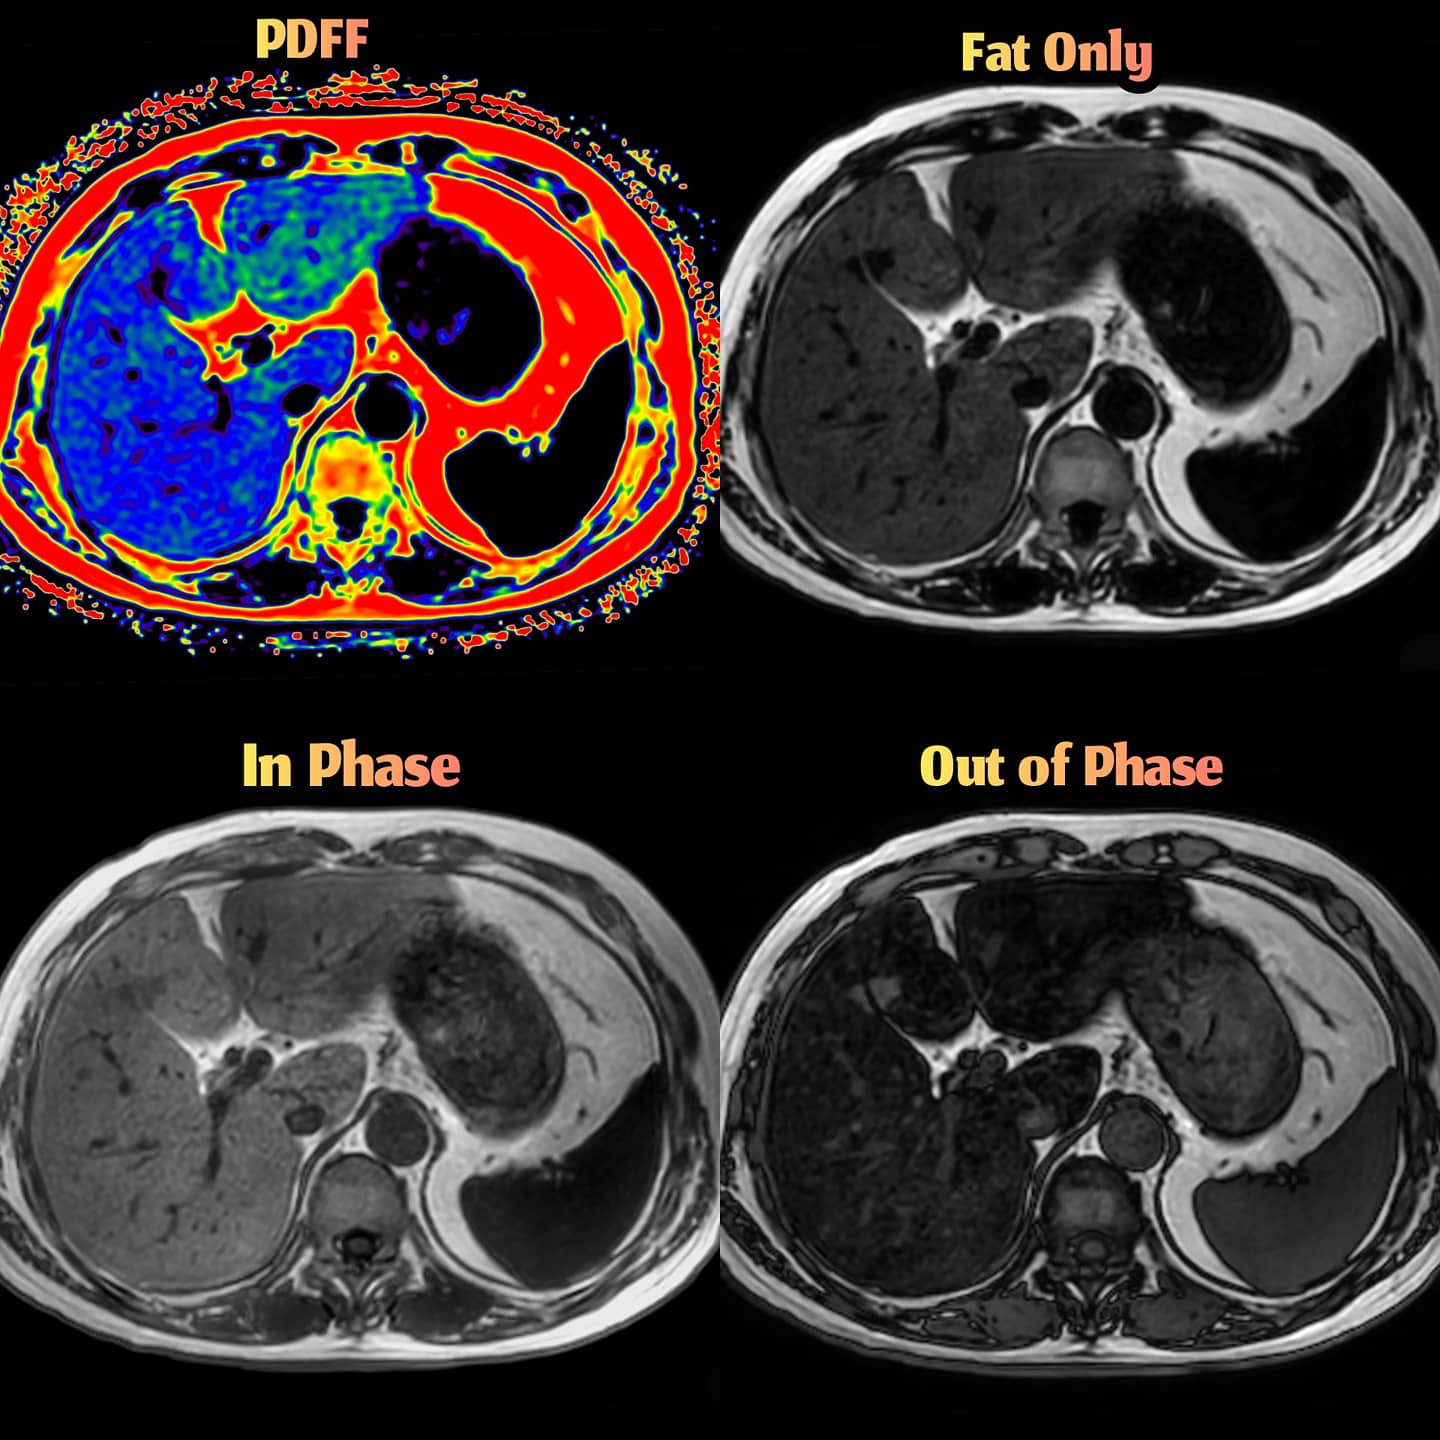

Fat fraction maps of a 54yearold subject. This subject's liver fat... Download Scientific Liver Fat Fraction The fat fraction should be used if both echoes are. The assessment of liver percentage fat fraction (%ff) using proton density fat fraction sequences is becoming increasingly. Liver Fat Fraction.